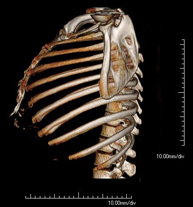

Exploració radiològica que mitjançant un sistema de raigs X i detectors que giren al voltant del pacient i que reconstrueixen les imatges per ordinador, permet l'estudi detallat detalla de la Parrilla. - Angio- TC Cardíac o TC Cardíac